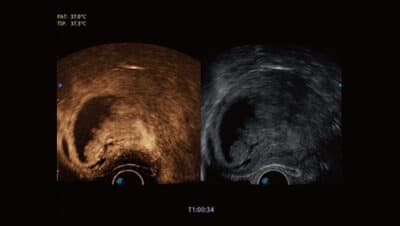

Pánevní dno 4D

Poskytuje užitečné klinické hodnocení pro posouzení přítomnosti a rozsahu prolapsu pánevních orgánů.

Velký pomocník v poporodní péči o ženy.